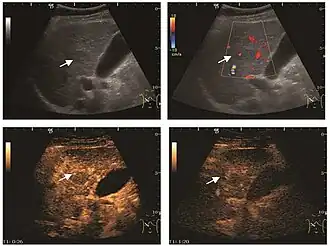

The ultrasound appearance is a well defined lesion, with very thin, almost unapparent walls, without circulatory signal at Doppler or CEUS investigation. The content is transonic suggesting fluid composition. The presence of membranes, abundant sediment or cysts inside is suggestive for parasitic, hydatid nature. Posterior from the lesion the acoustic enhancement phenomenon is seen, which strengthens the suspicion of fluid mass. They typically displace normal liver vessels but no vascular or biliary invasion occurs.

Hydatid liver cyst. Diagnostic criteria are the presence of membranes and sediment inside.